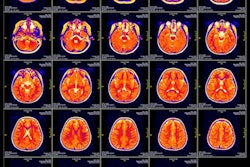

Contrast-enhanced MR image of the abdominal aorta, renal arteries, and kidneys of a baboon acquired with the manganese-based agent Mn-PyC3A (left), compared with the same scan with a gadolinium-based contrast agent (right). Images courtesy of Eric Gale, PhD.Gadolinium, on the other hand, is not naturally found in the human body, and recent studies have raised questions about whether there are long-term adverse effects due to the metal's retention in the brain and other tissue years after a GBCA-enhanced MRI scan.

In the current study, the researchers compared Mn-PyC3A with a commonly used GBCA in a baboon model. Each animal underwent two MRI scans under identical conditions -- one with Mn-PyC3A and one with the GBCA. The dosages and imaging protocols were the same as those used for human patients.